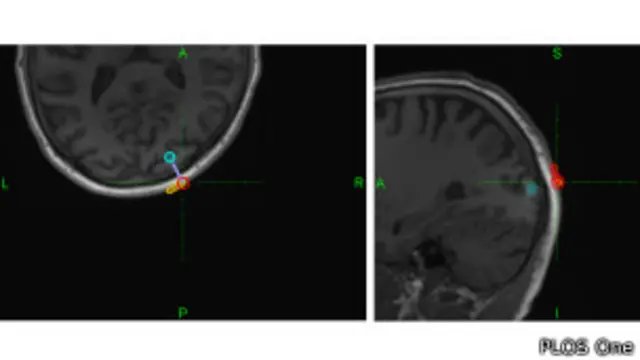

"En el caso de este experimento tuvimos al sujeto emisor imaginando dos tipos de movimiento, y esto puede ser detectado y clasificado por una computadora y enviado a través de internet a otro dispositivo que se usa básicamente para pulsar un lugar en el córtex, en el cuero cabelludo de una persona, con una técnica que se llama estimulación magnética transcraneal, que permite al sujeto receptor percibir una luz", dijo el investigador.

Cabe aclarar que estas técnicas no son invasivas, es decir, se aplican por fuera del cráneo.

"El receptor está sentado pasivamente en una silla y un robot configura un dispositivo que pulsa el cerebro suavemente con los parámetros correctos o incorrectos, y esto el sujeto lo reporta diciendo 'he visto luz o no he visto luz’", dijo Ruffini, responsable de la empresa Starlab, una de las tres que participaron de la prueba que reunió a científicos de las universidades de Barcelona, en España, y de Harvard, en EE.UU.

Fuente de la imagen, PLOS One

El emisor en la India pensó "hola" en lenguaje binario: 0 0 1 1 1 - 0 1 1 0 1 - 0 1 0 1 0 - 0 0 0 0 0, esas "letras" fueron leídas como pulsos eléctricos que se codificaron para transmitirse por internet y se volvieron a convertir en pulsos para producir una descarga electromagnética sobre la corteza cerebral del receptor, sentado en su silla en Estrasburgo.